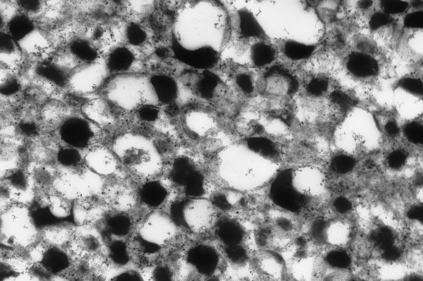

ADRENAL MEDULLA

Histologically, the adrenal medulla consists of chromaffin cells (so called because they produce brown pigments when fixed in solutions of chrome salts) and sympathetic nerve endings. The adrenal medulla is the main source of adrenaline (epinephrine), as it is produced there from noradrenaline (norepinephrine) by the enzyme phenylethanolamine-N-methyl transferase. Elsewhere in the body, sympathetic nerve endings lack this enzyme and their secretory product is thus noradrenaline. Electron microscopy reveals electron-dense granules in the chromaffin cells (Fig. 17.8), similar to those found in other tissues of the so-called amine precursor uptake and decarboxylation (APUD) system. Islands of similar tissue, known as the organs of Zuckerkandl, are sometimes found in other retroperitoneal sites; these have similar functions and a similar pattern of diseases to that seen in the adrenal medulla. Catecholamines are secreted in states of stress and of hypovolaemic shock, when they are vital in the maintenance of blood pressure by causing vasoconstriction in the skin, gut and skeletal muscles. At tissue level, these hormones bind to cell surface receptors, altering cellular levels of a second messenger, cyclic AMP, which brings about rapid functional changes in the cell.

image

Fig. 17.8 Electron micrograph of noradrenaline granules in a chromaffin cell. The granules characteristically have eccentric electron-dense cores (× 75 000).